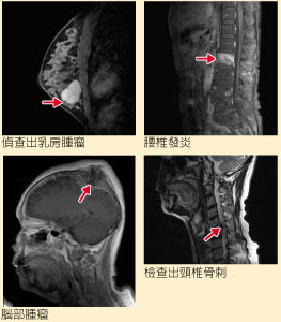

颈、腰、胸椎、脑血管疾病及乳癌筛检

磁振造影是利用体内氢原子在强大磁场内受电磁波激发而释放的讯息来成像。所以磁振造影没有令人担心的辐射线,可做全身癌症筛检,能在短时间内进行全身扫描。传统X光或计算机断层扫描无法侦测出的疾病,都可利用磁振造影来达到早期发现、早期治疗的目的。

。安全性:没有令人担心的辐射线,孕妇也可接受检查 。快速性:本院MRI是高磁场新机型,可快速取得诊断影像,大幅降低检查时间 。特殊性:核磁共振血管摄影可清楚呈现主要动脉血管,避免传统血管摄影可能造成的疼痛及并发症。对于颈、腰、胸椎的微小病变或椎间盘突出所引起的问题都有极高的侦查率 。高分辨率:提供更精确、更高分倍的分辨率诊断影像